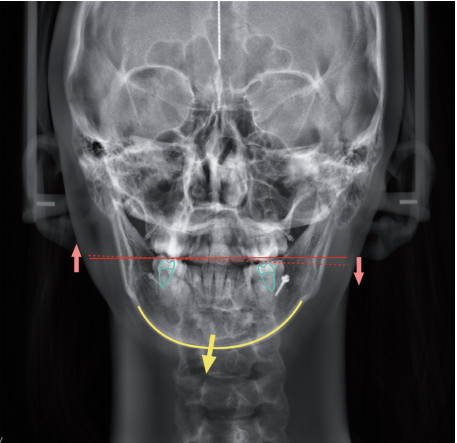

就像这位女士主诉自己上下中线不齐,牙齿锁颌,前牙有缝,下巴偏左,影响美观,想要通过牙齿矫正改善牙齿和面型存在的问题。

另外在牙齿矫正过程中,需要下颌颏部向右移动,在下颌颏点正中位置与面部正中线一致的基础上,后牙区垫颌垫,稳定下颌位置。

口内:上下颌中线对齐、左侧咬合恢复正常,因为去除了左侧咬合干扰,偏颌的情况得到了很好的改善。